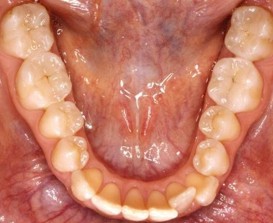

Kunststoffe

Mit modernen Kunststoffen können auch Seitenzähne

bis zu einer bestimmten Größe gefüllt werden.

Durch eine aufwändige Verarbeitung wird ein direkter

Verbund mit dem Zahn hergestellt.

Die modernen Kunststoffe (Composite) bestehen zu 80% aus

Keramik, die dem Material Stabilität und natürliches

Farbverhalten verleihen. Composite erreichen in Härte

und Abriebverhalten Zahnschmelzniveau. |